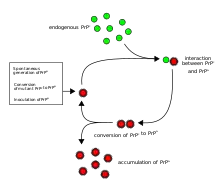

The first hypothesis that tried to explain how prions replicate in a protein-only manner was the heterodimer model.[52] This model assumed that a single PrPSc molecule binds to a single PrPC molecule and catalyzes its conversion into PrPSc. The two PrPSc molecules then come apart and can go on to convert more PrPC. However, a model of prion replication must explain both how prions propagate, and why their spontaneous appearance is so rare. Manfred Eigen showed that the heterodimer model requires PrPSc to be an extraordinarily effective catalyst, increasing the rate of the conversion reaction by a factor of around 1015.[53] This problem does not arise if PrPSc exists only in aggregated forms such as amyloid, where cooperativity may act as a barrier to spontaneous conversion. What is more, despite considerable effort, infectious monomeric PrPSc has never been isolated.

An alternative model assumes that PrPSc exists only as fibrils, and that fibril ends bind PrPC and convert it into PrPSc. If this were all, then the quantity of prions would increase linearly, forming ever longer fibrils. But exponential growth of both PrPSc and of the quantity of infectious particles is observed during prion disease.[54][55][56] This can be explained by taking into account fibril breakage.[57] A mathematical solution for the exponential growth rate resulting from the combination of fibril growth and fibril breakage has been found.[58] The exponential growth rate depends largely on the square root of the PrPC concentration.[58] The incubation period is determined by the exponential growth rate, and in vivo data on prion diseases in transgenic mice match this prediction.[58] The same square root dependence is also seen in vitro in experiments with a variety of different amyloid proteins.[59]

Until 2015 all known mammalian prion diseases were considered to be caused by the prion protein, PrP; in 2015 multiple system atrophy was found to be transmissible and was hypothesized to be caused by a new prion, the misfolded form of a protein called alpha-synuclein.[10] The endogenous, properly folded form of the prion protein is denoted PrPC (for Common or Cellular), whereas the disease-linked, misfolded form is denoted PrPSc (for Scrapie), after one of the diseases first linked to prions and neurodegeneration.[35][16] The precise structure of the prion is not known, though they can be formed spontaneously by combining PrPC, homopolymeric polyadenylic acid, and lipids in a protein misfolding cyclic amplification (PMCA) reaction even in the absence of pre-existing infectious prions.[61] This result is further evidence that prion replication does not require genetic information.[78]

Transmission

It has been recognized that prion diseases can arise in three different ways: acquired, familial, or sporadic.[79] It is often assumed that the diseased form directly interacts with the normal form to make it rearrange its structure. One idea, the "Protein X" hypothesis, is that an as-yet unidentified cellular protein (Protein X) enables the conversion of PrPC to PrPSc by bringing a molecule of each of the two together into a complex.[80]